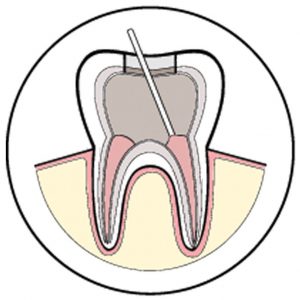

Root Canal Therapy

Root Canal Therapy is a treatment performed to save a tooth that has been badly damaged due to decay, disease or injury.